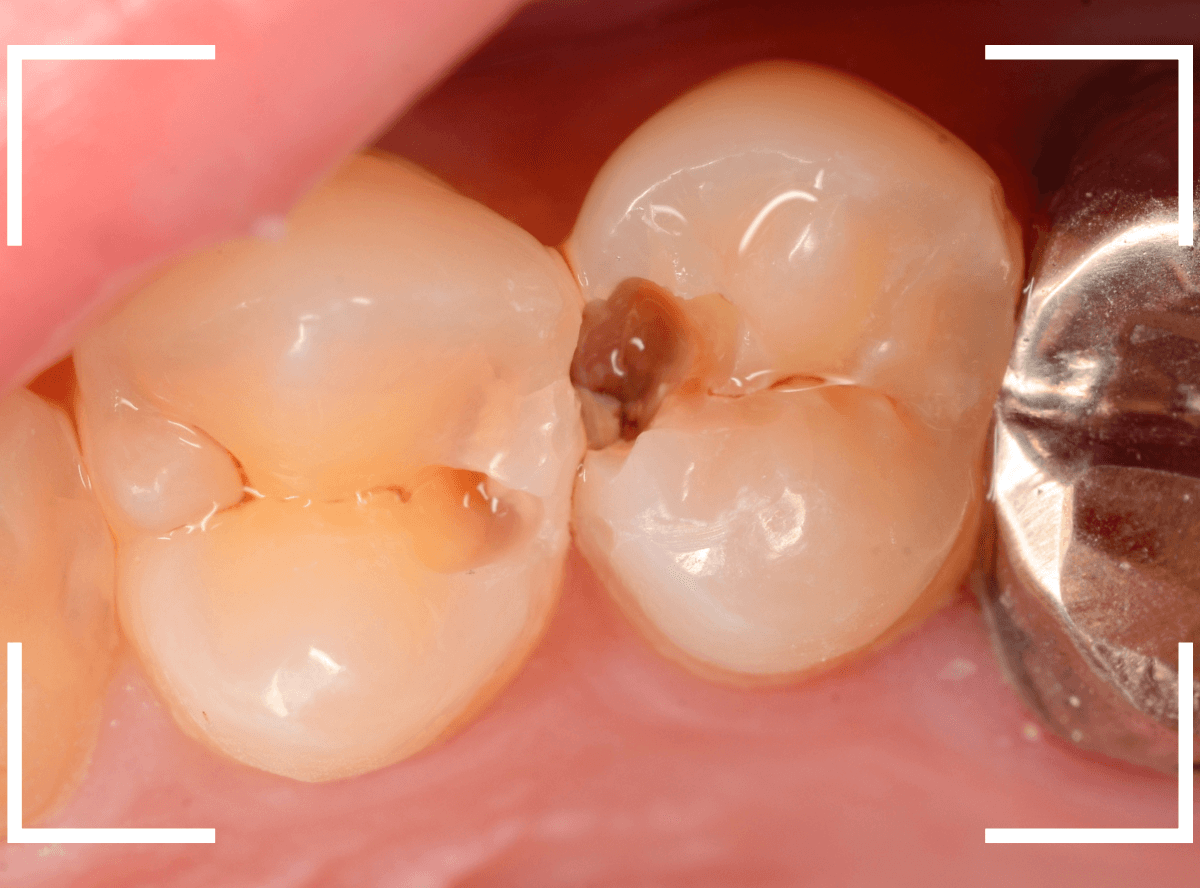

Case.21 神経に達しそうな2本の大きな虫歯

上の小臼歯の側面が明らかに虫歯になっている患者さんです。

患者さんは特に症状を感じてなさそうですが、恐らくは中で大きな虫歯になっているでしょう。

このように、自覚症状からだけでは虫歯の状況は診できません。

まず、奥の歯のつめものを外してから、虫歯の治療を開始します。

手前の歯が大きな虫歯が見えてきました。